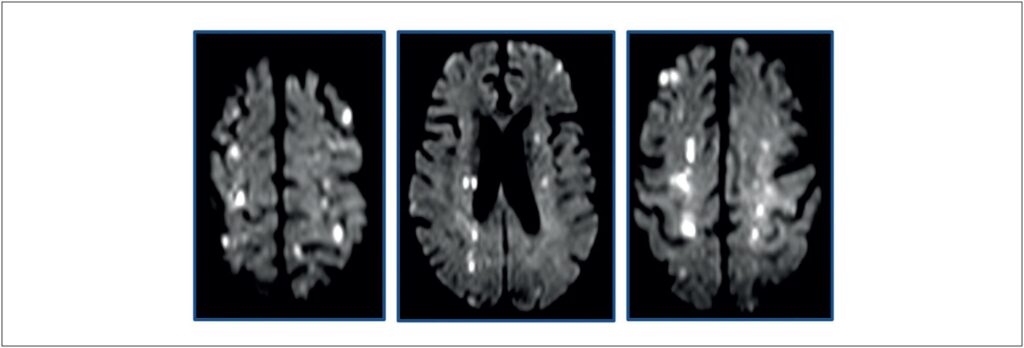

Valvulite Aórtica na Síndrome Hipereosinofílica: Relato de Caso

Palavras-chave: Acidente Vascular Cerebral; Síndrome Hipereosinofílica; Valvopatia Aórtica